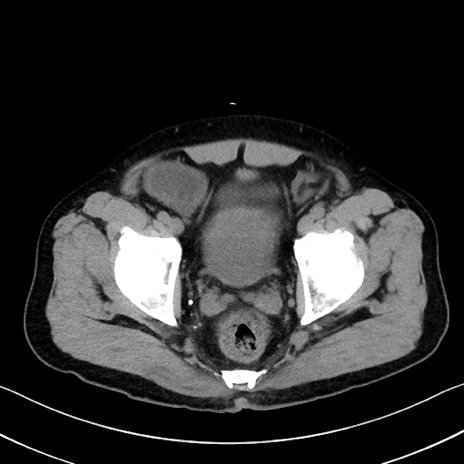

症例35(横断像)

【症例】70歳代 男性

【主訴】腹部膨満、嘔吐

【現病歴】昨日より腹部膨満感出現。本日増悪し、仙痛出現。嘔吐あり、受診。

【既往歴】糖尿病、胆摘後

【身体所見】BP 149/80mmHg、HR 74/min、BT 35.9℃、腹部:膨満、軟、圧痛なし。腸雑音減弱あり。上腹部正中切開瘢痕あり。

【データ】WBC 13500、CRP 1.72